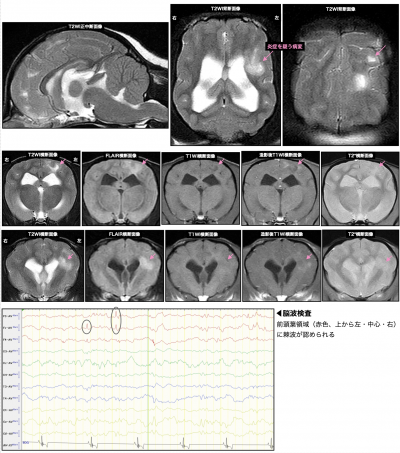

MRIと脳脊髄液検査では、大脳に壊死性白質脳炎を疑う所見が認められました。また、病変部位に一致する脳領域にてんかん性異常脳波(スパイクや鋭波と呼ばれる)が認められました。

これらの所見から、「壊死性白質脳炎(NLE)を病因とした構造的てんかん」と診断しました。

症例のMRIと脳波所見